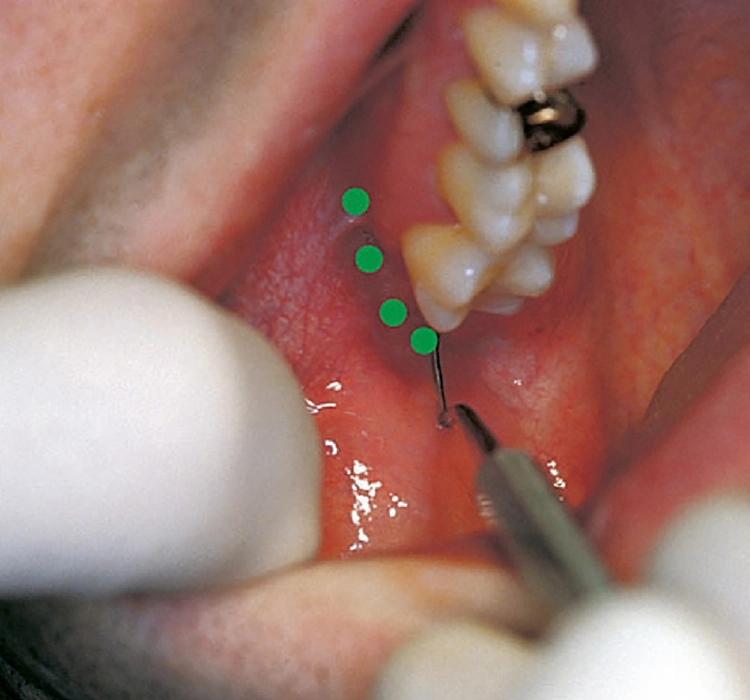

Für die Mundakupunktur gilt, dass die therapeutischen Möglichkeiten ihr Optimum haben in der Retromolarregion, einem besonderen Reflexareal. Die breite Wirkung der Retromolartherapie bei der CMD ist belegt durch klinische Studien an den Kieferkliniken Wien und München, ebenso wie durch die über 40-jährige Erfahrung von Gleditsch und die Rückmeldungen von Hunderten in Seminaren geschulten Zahnärzten. Mittels gezielter Injektionen an Schleimhautpunkte distal der Weisheitszähne (sog. „Neuner-Gebiet“) können Anteile bzw. Ansätze der Pterygoidmuskeln erreicht und entspannt werden.

Japanische Forscher konnten mittels Tracer-Färbe-Technik nachweisen, dass von der Schleimhaut des Gaumenbogens – dicht an der Plica pterygomandibularis – direkte nervale Verbindungen bestehen zum obersten Ganglion des Sympathikus-Grenzstrangs: Das Ganglion zervikale kraniale gilt als wichtige Schaltzentrale der autonomen Regulation für den Kopf-Hals-Bereich, was die breite Wirkung der Retromolartherapie erklärt. Die Erfahrung zeigt, dass oberflächlich gesetzte Miniquaddeln wirksamer sind als Überflutung und tiefe Injektionen. Bewährt haben sich schwachprozentige, submukös injizierte Lokalanästhetika (z.B. Procain 0,5%).

Diese Minidosentherapie findet eine Parallele in der in Frankreich weit verbreiteten Mesotherapie, bei der wenige Tropfen einer Medikamentenmixtur – einige Lokalanästhetika-Tropfen sind jeweils dabei – intrakutan dicht nebeneinander appliziert werden; die Nadel streicht hierbei, ohne abzusetzen, über das Areal (sog. Salveninjektion). Diese Technik eignet sich auch für die Retromolartherapie und wird von den HNO-Kollegen bevorzugt.